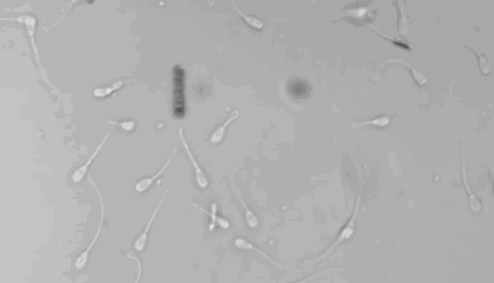

如果能像遥控玩具车一样,让小蝌蚪的方向掌握在你的手柄上,还愁它找不到妈么?所以,下面让我们热烈欢迎德国科学家最新力作 —— 精子机器人,隆重登场。

没看清?放大一点再看!!!

用它管理小蝌蚪,蝌蚪们就会跟着遥控,你想让它们去哪里就去哪里!